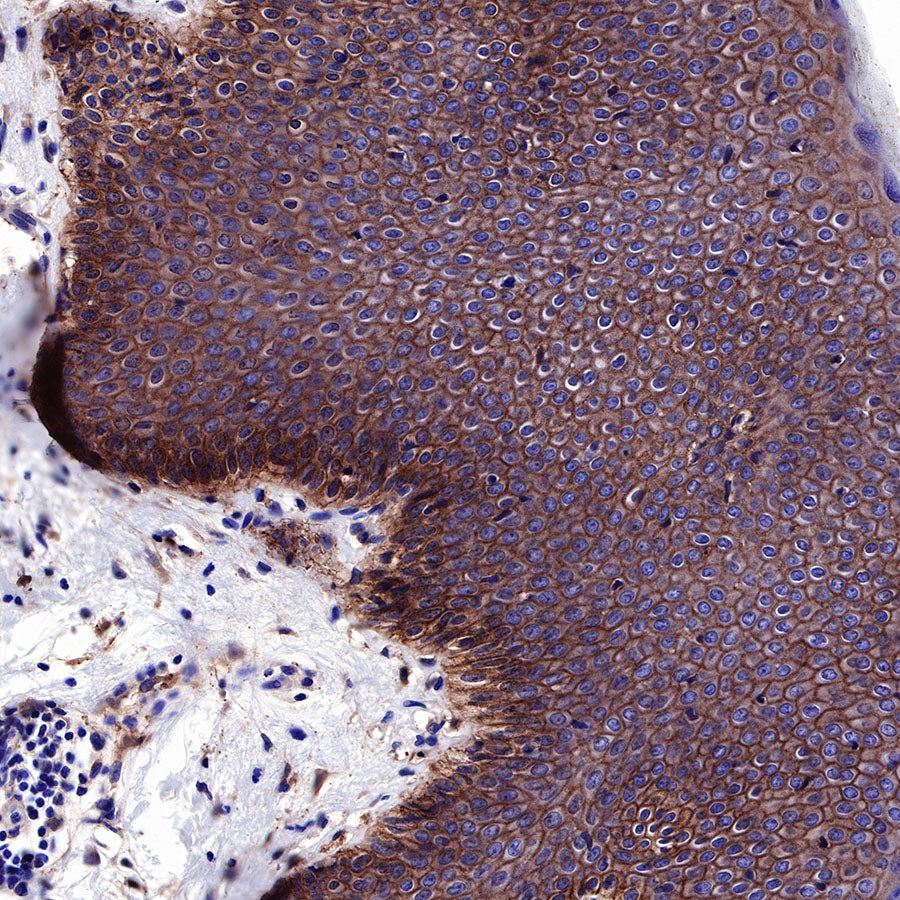

Immunohistochemistry

IHC shows positive staining in paraffin-embedded human skin. Anti-EGFR antibody was used at 1/2000 dilution, followed by a HRP Polymer for Mouse & Rabbit IgG (ready to use). Counterstained with hematoxylin. Heat mediated antigen retrieval with Tris/EDTA buffer pH9.0 was performed before commencing with IHC staining protocol.